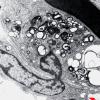

PERIPHERAL NEUROPATHY

7B CIDP (2)